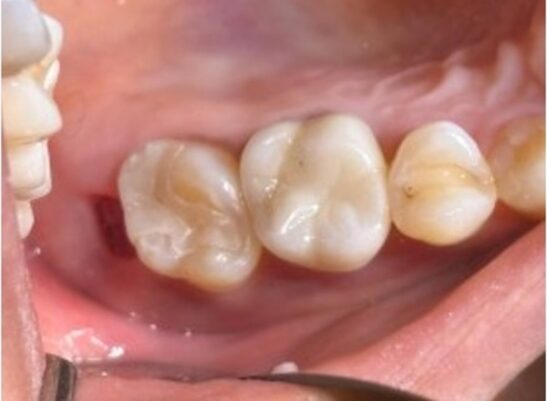

右側上顎には仮歯が装着されており、その後方の歯には虫歯が認められました。さらにその後方には親知らずが生えており、来院時は多量の汚れがついていました。

上顎右側は治療中であり前方から第一大臼歯は仮歯、第二大臼歯は虫歯その後方には親知らずが生えているという状態でした。

完成したZenoスタークラウンとZenoスターインレーの調整を行い、同時に装着しました。装着時にシミ等の痛みの症状はみられませんでした。

治療後の様子

2週間後に来院していただき、噛み合わせの確認を行いました。特に違和感なく経過し、噛み合わせの診査においても問題は認められなかったため定期検査に移行しました。